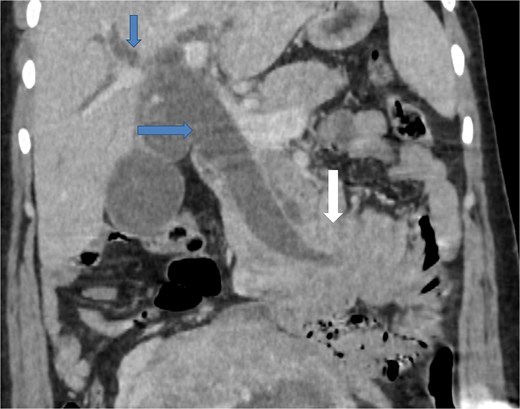

Due to the acute presentation and unavailability of emergency magnetic resonance imaging (MRI), a contrast-enhanced computed tomography (CT) scan of the abdomen was performed with strict fetal protection measures (lead apron, low-dose protocol). The pancreas appeared normal with no signs of inflammation, necrosis, or peripancreatic fluid. Unexpectedly, the scan revealed a duodenojejunal intussusception, likely originating from the fourth portion of the duodenum (D4), involving invagination of a proximal jejunal loop (Fig. 1). A typical pseudokidney sign was observed on sagittal reconstructions (Fig. 2). There was no identifiable lead point such as a mass or polyp. The intussusception was seen tractioning the distal common bile duct, leading to marked extra- and intrahepatic bile duct dilatation (Fig. 3).

Sagittal contrast-enhanced CT images (a, b) showing the duodenojejunal intussusception with a pseudokidney appearance (arrows).